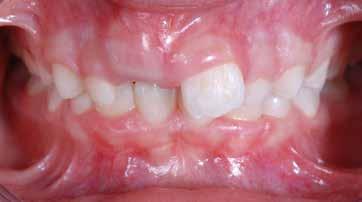

B.M. Bambina di sei anni e mezzo, con malocclusione scheletrica di II Classe, deep-bite over-jet elevato, lieve contrazione dell’arcata superiore, alterazione dell’eruzione dell’elemento dentale 21.

Fig. 119 > Immagine extraorale frontale.

Fig. 120 > Immagine extraorale frontale con sorriso.

Fig. 121 > Particolare del sorriso.

Fig. 122 > Immagine intraorale frontale.

Fig. 123 > Immagine intraorale laterale destra.

Fig. 124 > Immagine intraorale laterale sinistra.

Fig. 125 > Immagine occlusale superiore.

Fig. 126 > Immagine occlusale inferiore.